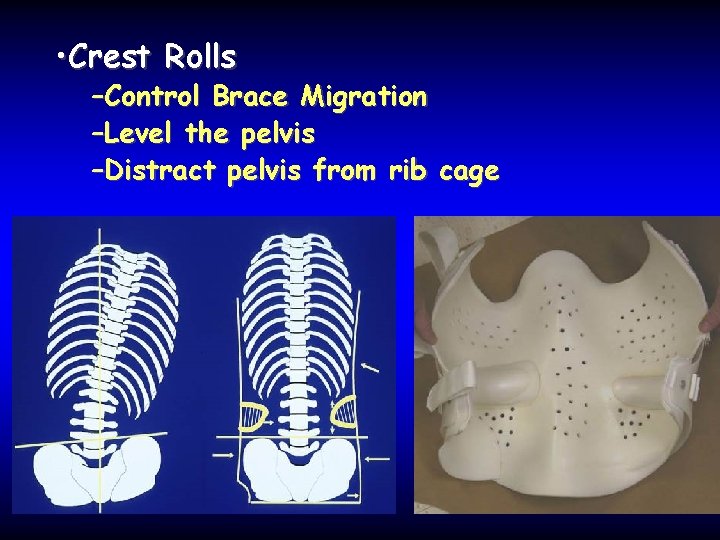

• Crest Rolls –Control Brace Migration –Level the pelvis –Distract pelvis from rib cage